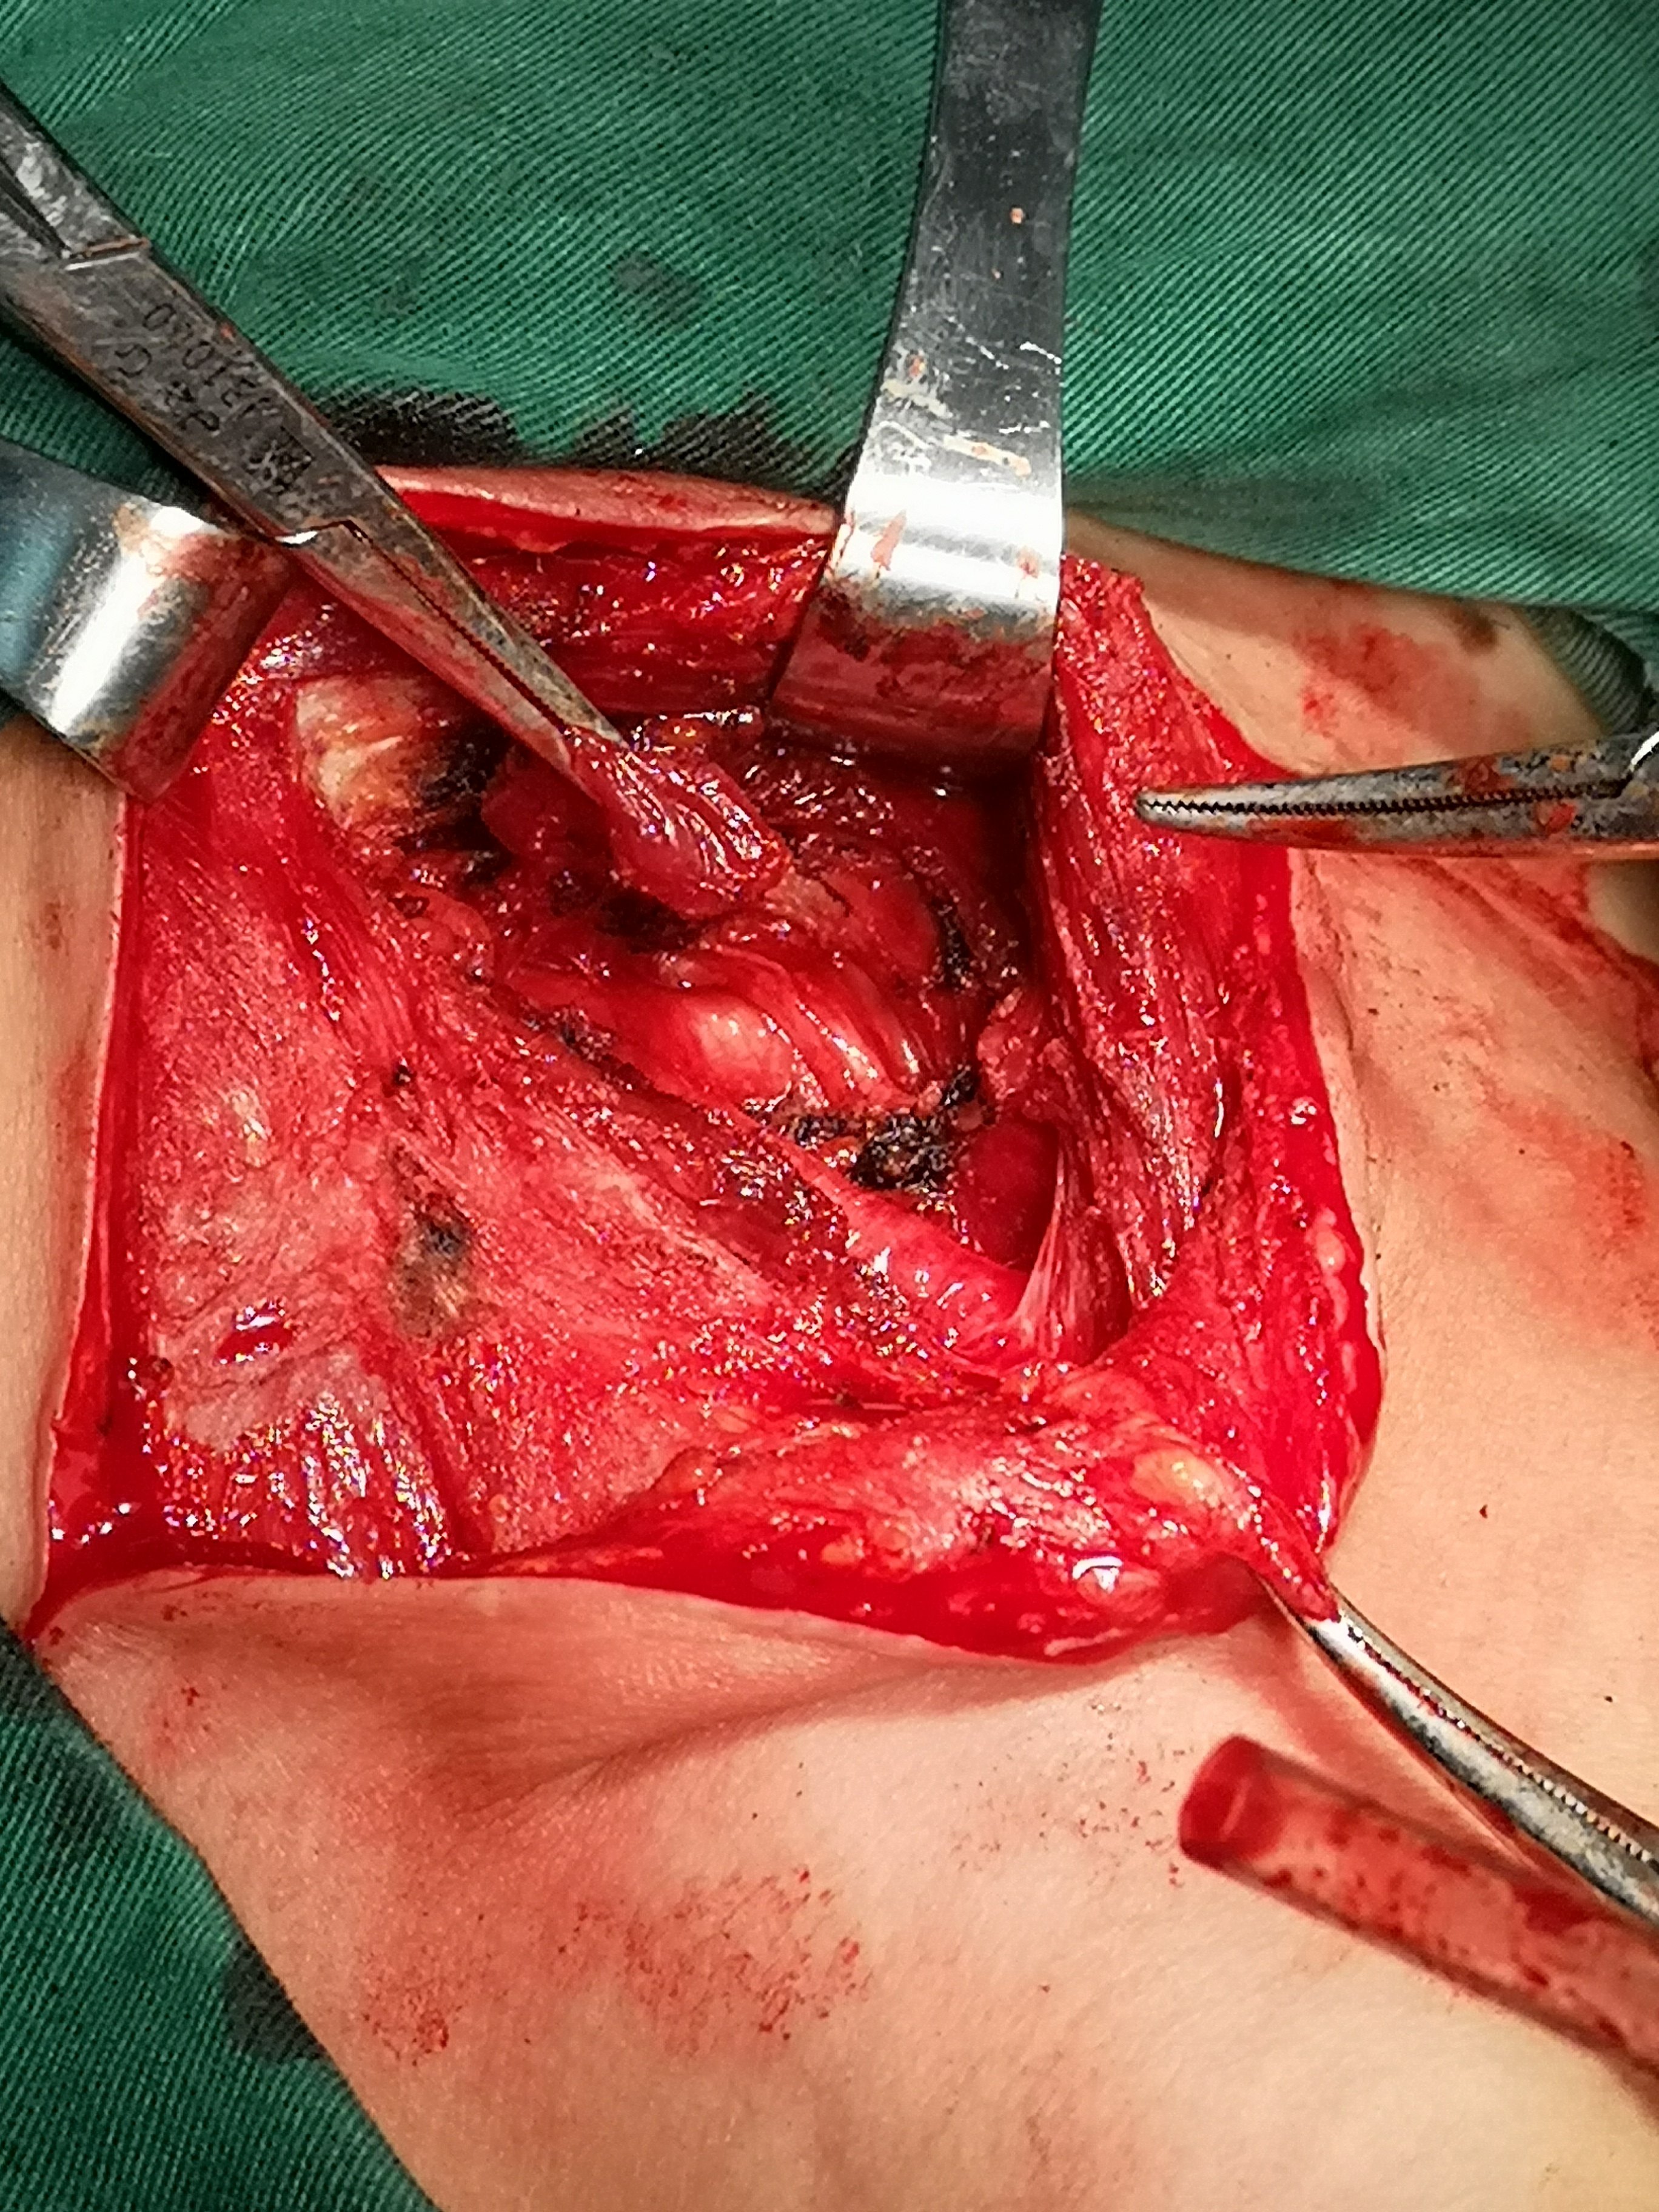

甲状腺癌再次手术

病例2 右2,右4R区,左6区残留,颈部切口清扫,未开胸